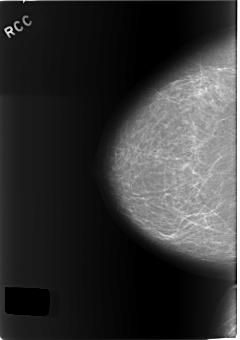

C_0160_1.RIGHT_CC

RIGHT_CC LINES 5776 PIXELS_PER_LINE 4064 BITS_PER_PIXEL 12 RESOLUTION 50 NON_OVERLAY